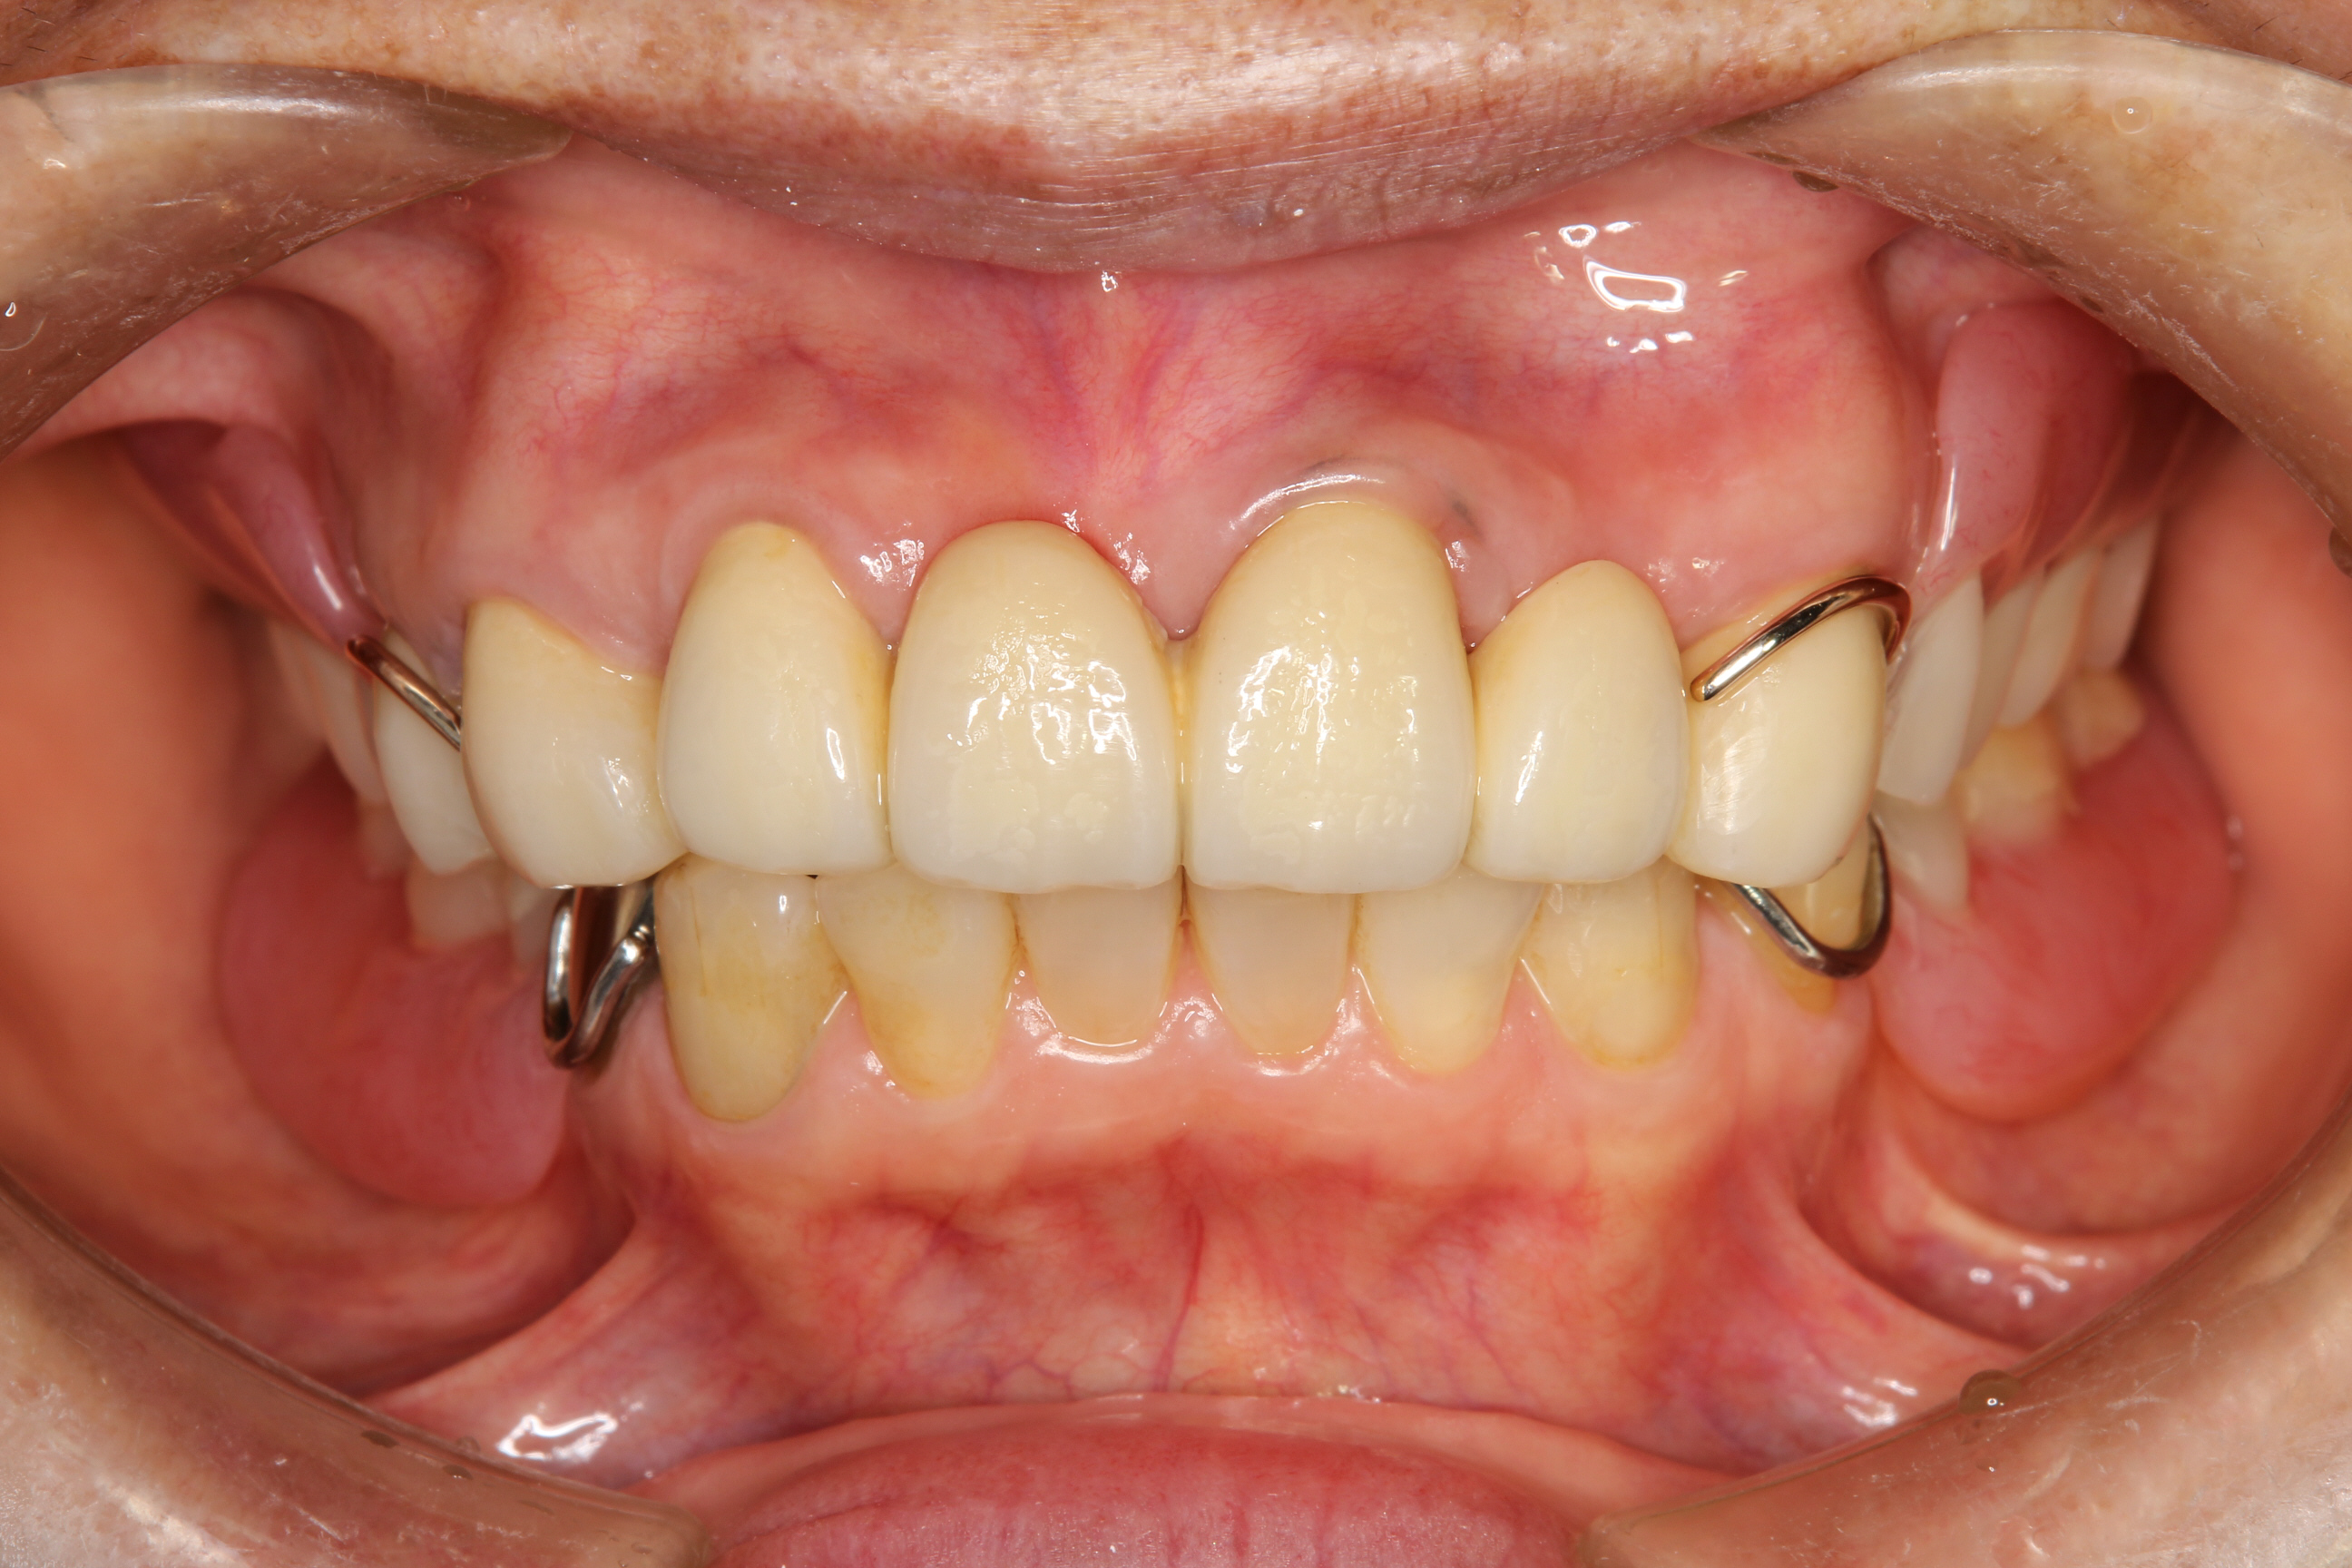

こちらが治療後の写真です。

上顎前歯部はブリッジにて機能を回復。臼歯(奥歯)の欠損部は部分義歯を装着しています。

前歯のブリッジは、奥に入る義歯の維持安定を図るための形態を付与しており、これにより義歯が安定し前歯への負担も最小限となることで、歯や補綴物(ブリッジや義歯)が壊れることなく守られるのです。

低くなってしまっていた噛みあわせも改善し、正面から見た時のバランスも良くなりました。

患者さんも、「これで歯を隠さないでも笑える」 と喜んでおられました。